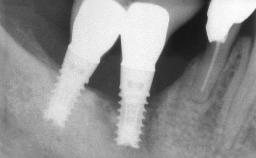

Oral implants are highly successful and offer long-term benefits, especially in the rehabilitation of edentulous patients or patients with oral defects following ablative tumor surgery (Albrektsson and coworkers 1986), and also after radiation therapy (Schiegnitz and coworkers 2014). With the number of implants placed globally going into the millions, implant dentists have observed some rare adverse events. Although carcinogenesis around implants is an exceedingly rare phenomenon, we recently reported about 15 patients treated for carcinomas adjacent to implants at our clinical department over a period of fifteen years (Moergel and coworkers 2014). The following case represents a patient of this cohort; it discusses possible risk factors and makes suggestions for a recall schedule. A 70-year-old woman was referred to our outpatient department for evaluation of a rapidly growing macroscopic alteration of the mucosa in the left mandible.